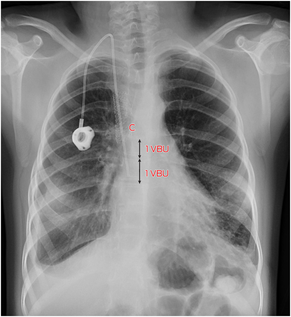

Although rarely life‐threatening, SVCS symptoms are distressing for the patient and it substantially complicates upper body vascular access, particularly if future organ transplantation or chronic renal replacement therapy is needed.5,9,10,11 Using oral instead of intravenous antibiotics with similar efficacy or use of leadless pacemakers without transvenous leads will reduce SVCS.5,9 If central venous access is required, it is important to use a catheter with the smallest diameter possible, for the shortest time, with the shortest intravenous course, and with careful catheter tip positioning.5,9,12 The superior cavoatrial junction is a safe catheter tip location, reproducibly identified on chest x‐ray as a point two vertebral body units below the carina (Box 3), where one vertebral body unit is one vertebral body and the superior adjacent vertebral disc.4,5 This is more inferior than commonly appreciated when looking at the superior aspect of the right heart border or right main bronchus on chest x‐ray.4

Box 3 – Chest x‐ray following new right internal jugular vein totally implantable venous access device (TIVAD) insertion through new stent graft with resolution of bilateral pleural effusions*

* Note the position of the catheter tip relative to the carina (C). One vertebral body unit (VBU = 1 vertebral body + 1 adjacent disc) is illustrated.